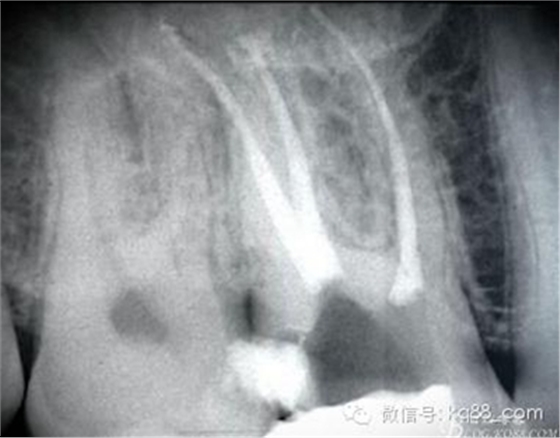

根管治療后X片